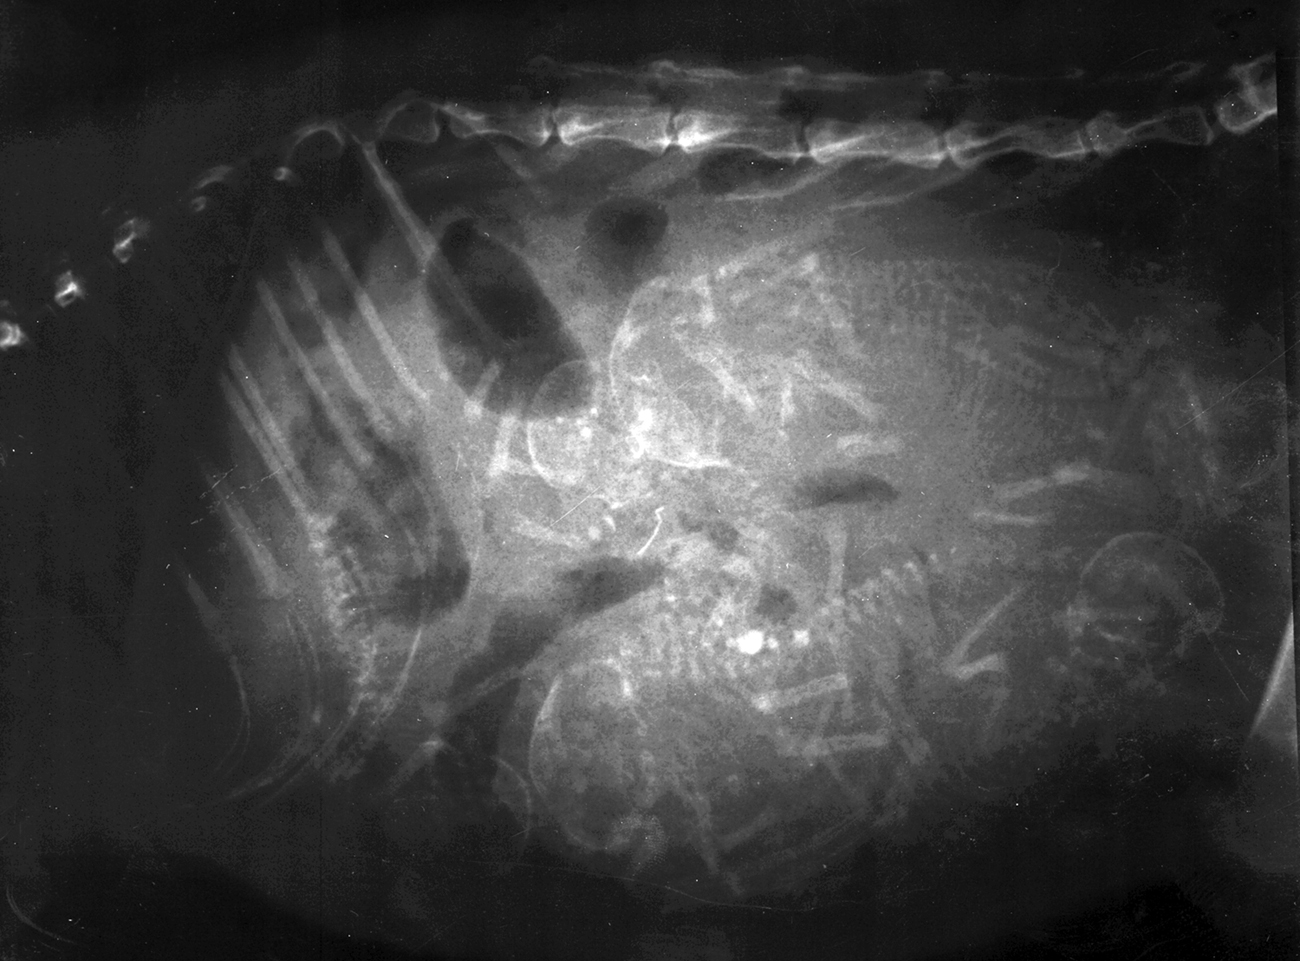

Her left front leg was limping.We found a punture there and was swollen, so she got an x-ray to be sure her leg wasn't broken. She also had a bad cold.

Attached is the scanned x-ray plaque.Could you guess how many babies she is carrying?